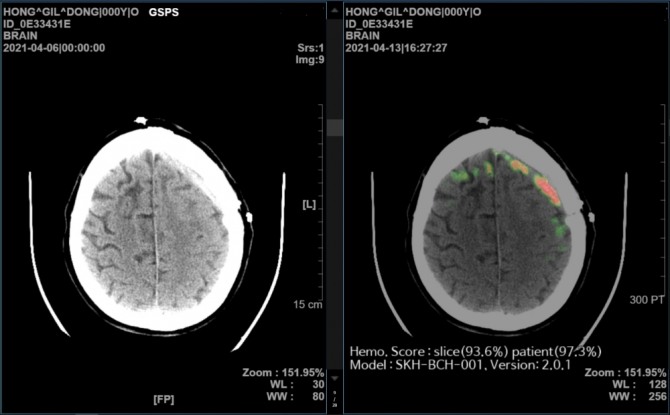

이미지 확대보기SK㈜ C&C는 ‘AI 뇌출혈 영상 의료 솔루션 효과성에 대한 논문’이 네이처 파트너 저널(Nature Partner Journals, npj)인 ‘디지털 메디신(Digital Medicine)’에 게재됐다고 3일 밝혔다.

‘메디컬 인사이트 플러스 뇌출혈’이 의료 기관별로 사용하는 다양한 CT장비 영상을 높은 수준의 정확도로 일관되게 분석한다는 점 또한 확인됐다.

한국지능정보화사회진흥원에서 구축한 약 5만명의 환자 데이터를 대상으로 ‘메디컬 인사이트 플러스 뇌출혈’의 AI 자체 진단 성능을 검증했을 때, GE, 필립스(Philips), 지멘스(Siemens), 도시바(Toshiba) CT 장비 모두에서 98~99%의 높은 진단 정확도를 보여줬다.

SK㈜ C&C의 메디컬 인사이트 플러스 뇌출혈은 2021년 AI 뇌출혈 진단 의료기기 중 국내 최초로 식품의약품안전처로부터 3등급 의료기기 품목 허가를 받았고 미국 FDA 허가를 위한 임상시험도 진행 중이다.